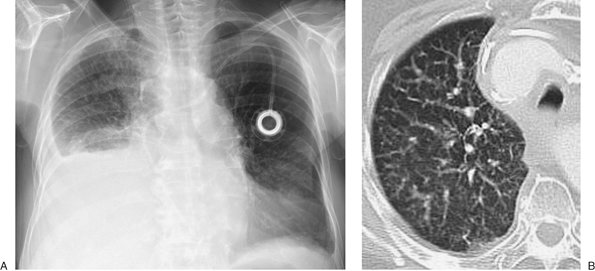

FIGURE 9-5. Cerebrospinal fluid leak into pleural space. A: PA chest radiograph of a 42-year-old man who recently underwent partial corpectomy of the thoracic spine at several levels shows complete opacification of the right hemithorax and shift of the mediastinum to the left. B: Non–contrast-enhanced CT shows a large right pleural effusion, collapse of the right lung, mediastinal shift to the left, findings of corpectomy, and continuity of fluid from the spine into the pleural space (arrow).

FIGURE 9-6. Pleural and pericardial effusions. A: PA chest radiograph of a woman with hypothyroidism shows blunting of the right costophrenic angle, producing a "meniscus" (arrow). B: Lateral chest radiograph shows blunting of both costophrenic angles posteriorly (arrow). C: CT shows bilateral pleural and pericardial effusions (E).

FIGURE 9-9. Positional appearances of pleural fluid on chest radiography and CT. A: PA upright chest radiograph shows apparent elevation of the right hemidiaphragm. The dome of the right hemidiaphragm appears to be displaced laterally (arrow), a clue to the diagnosis of pleural fluid collecting in a "subpulmonic" location. B: Anteroposterior (AP) supine chest radiograph of the same patient, 3 days later, shows hazy increased opacification of the right hemithorax secondary to pleural fluid layering posteriorly within the pleural space, now the most gravity-dependent portion of the pleural space. C: AP semi-upright chest radiograph of the same patient, 2 days after (B), shows a combination of pleural fluid layering posteriorly, which produces a hazy opacity in the mid and lower right hemithorax and laterally (arrows). D: Right lateral decubitus chest radiograph of the same patient, taken on the same day as (A), shows pleural fluid freely layering against the now gravity-dependent lateral chest wall, from the costophrenic angle to the lung apex (arrows). E: CT of the same patient, performed on the same day as (B), shows a moderate- to large-sized right pleural fluid collection (E), with associated "passive" atelectasis of the right lower lobe (A).